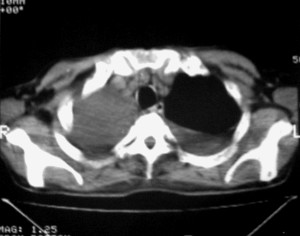

纵隔淋巴结增大,双侧胸水。考虑术后残留,而非复发。

肺癌术后 。双侧胸水 纵隔 胸膜 肝脏转移